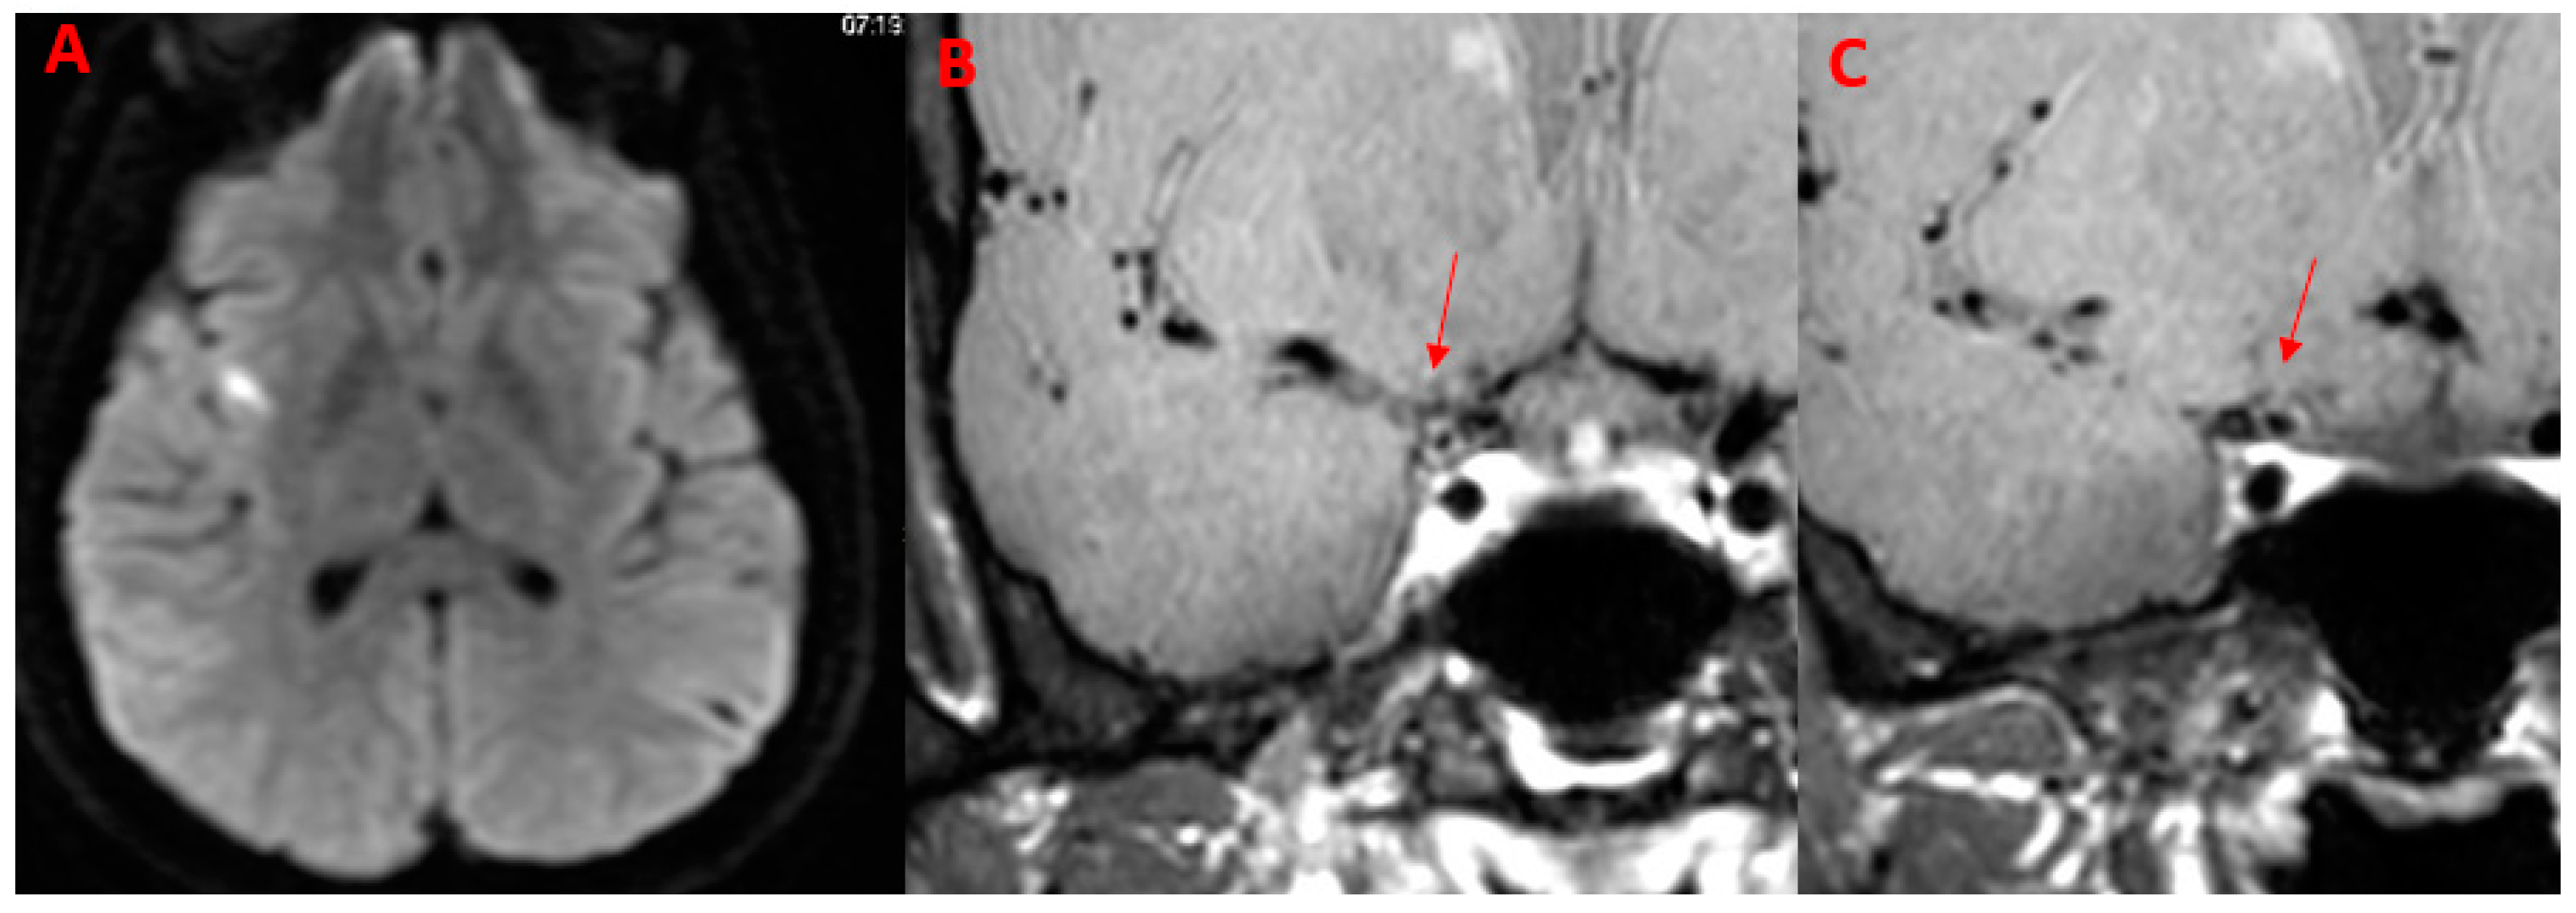

| 53Y, M | 1 | Present | Present | Fight corona radiata | ICA | ACOP | Present | Supratentorial |

| 63Y, M | 1 | Present | Present | Multiple Subcortical in ACA, MCA Territories and Pons | ACA (A2) | None | Present | Supratentorial, subtentorial |

| 29Y, F | // | Absent | Absent | No | ICA | ACA (A1), MCA (M1) | Absent | // |

| 32, M | // | Absent | Present | No | ICA | ACA (A1), MCA (M1) | Absent | // |

| PCNSV (n = 6) | 4 (66.7%) | 3 (50.0%) | 0 (0.0%) | 2 (33.33%) | 5 (83.3%) | 3 (50.0%) | 5 (83.3%) multiple: 2 (40.0%) | 4 (66.7%) | 0 (%) | 5 (83.3%) | 1 (16.7%) | MCA (M1, M2), ACA (A1, A2), ICA, ACOP |